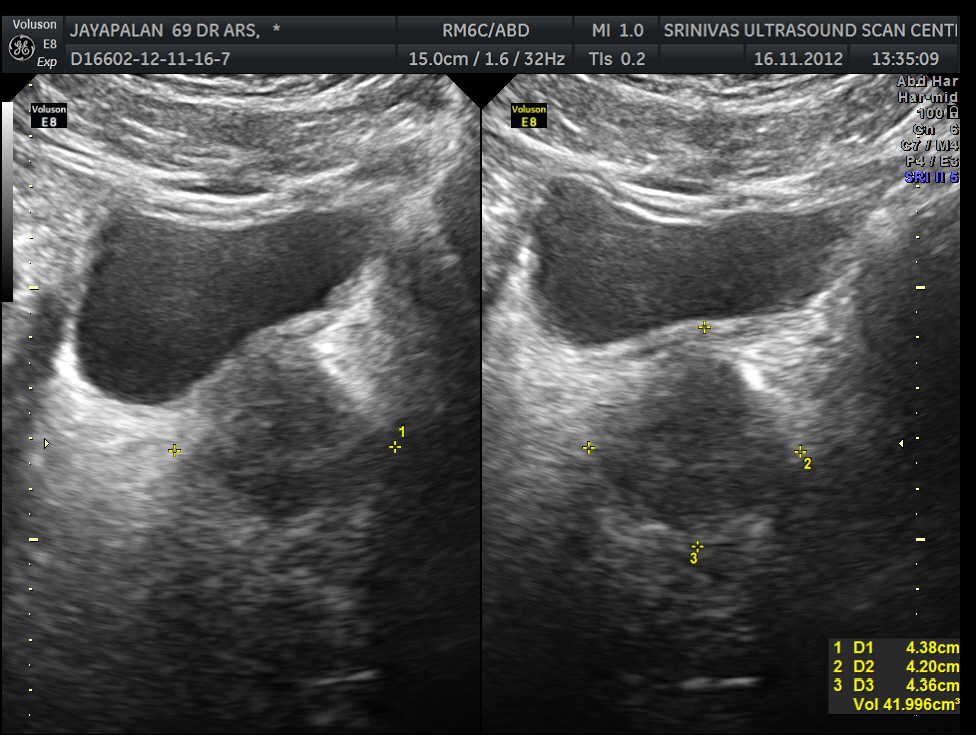

This was a 69 year old gentleman with right scrotal pain and swelling .Scan was requested to differentiate between epidydymo orchitis , testicular torsion or any mass lesion.

Colour doppler gives the answer instantly , Increased vascularity is epidydymo orchitis ; no vascularity with hypo echoic texture is torsion ; mass lesion can have localized increase of vascularity.

The following images were obtained . Power doppler and 3D reconstructed power doppler images show the increased vascularity very well.